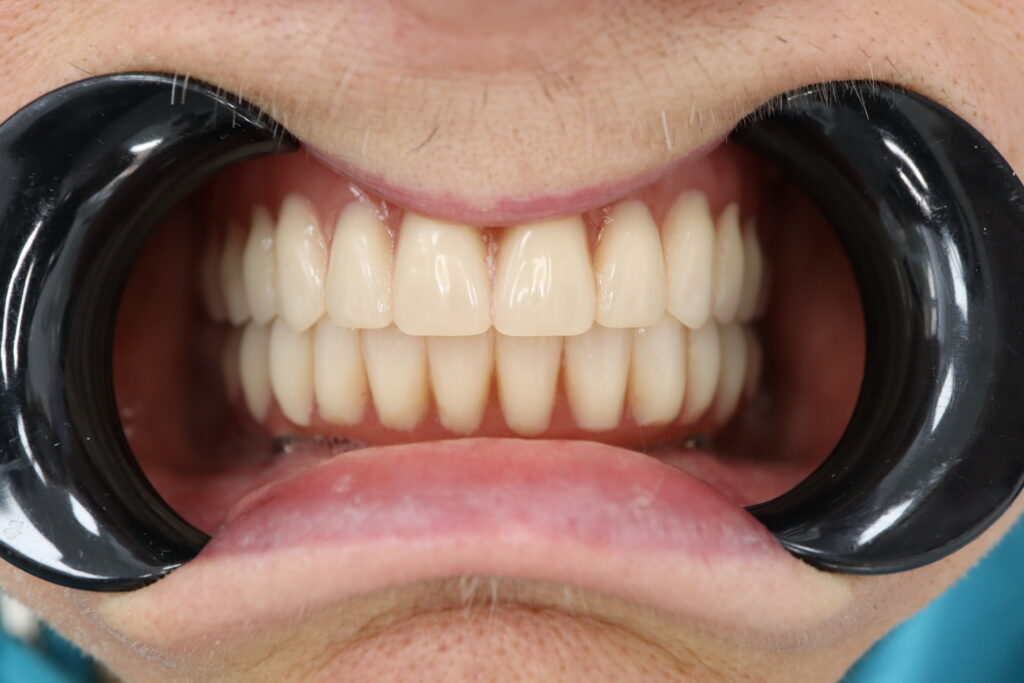

Спустя 7 дней на нижней челюсти зафиксирован металлоакриловый протез из 12 зубов с опорой на 4 дентальных имплантата.

На верхнюю челюсть изготовлен съемный акриловый протез.

результат